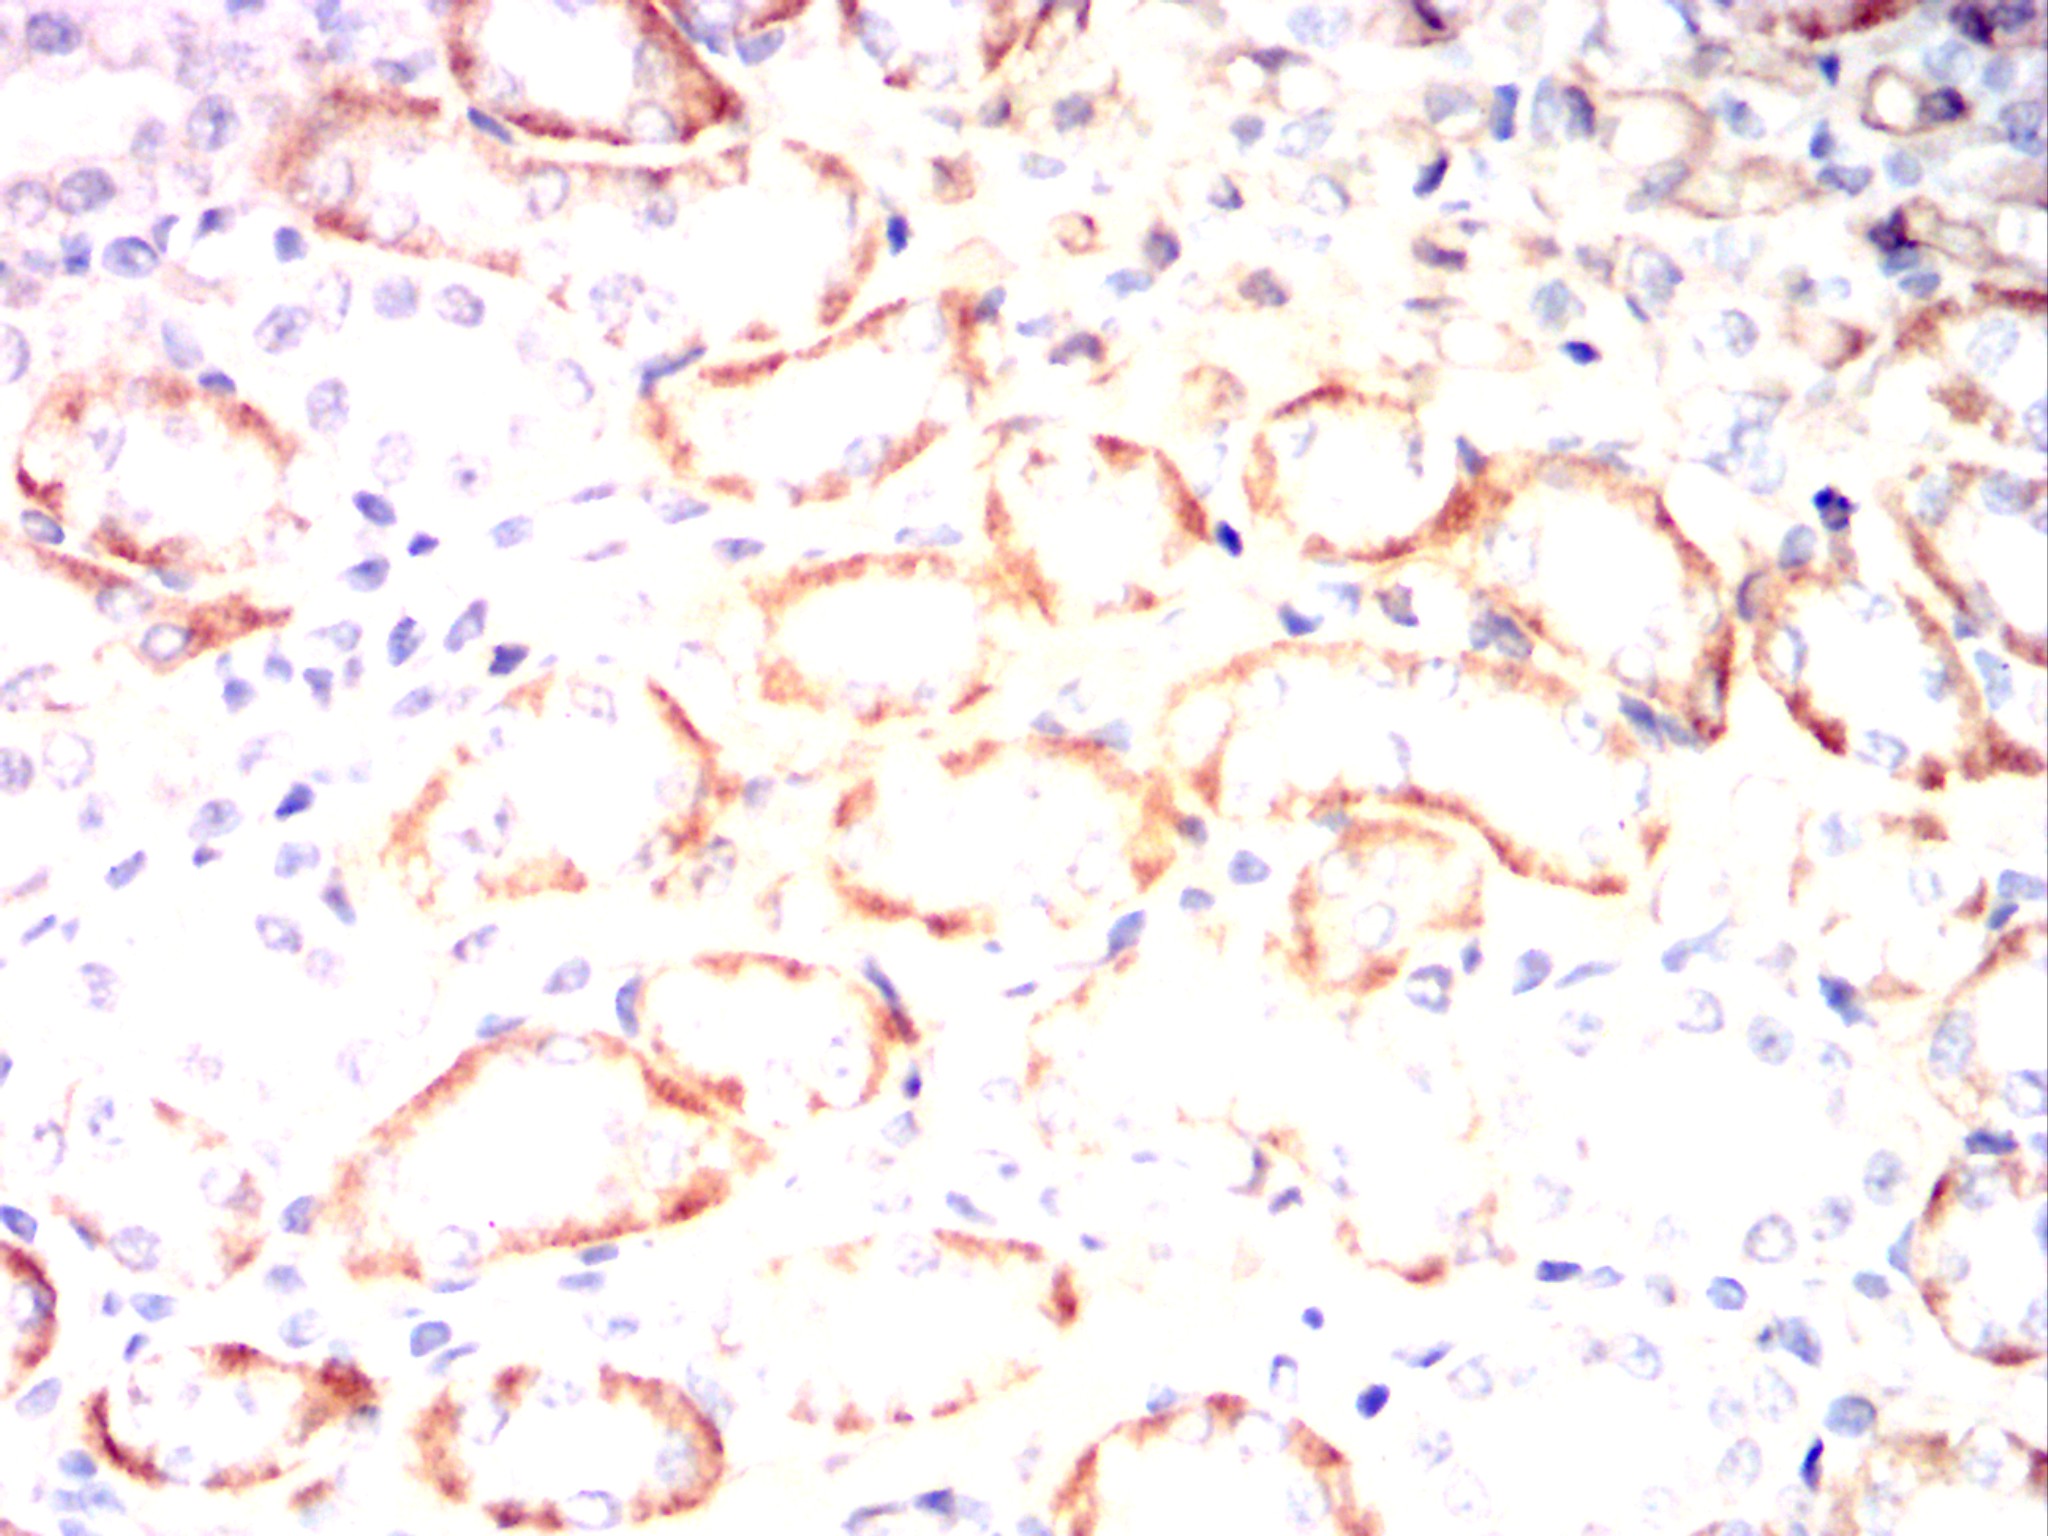

Immunohistochemical analysis of paraffin-embedded Mouse kidney using CD14 mouse mAb with DAB staining.